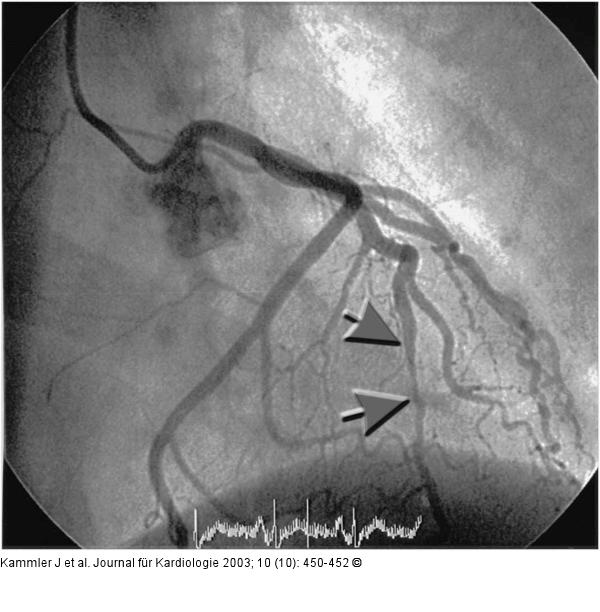

Abbildung 2: Systolische Komprimierung - Arteria coronaria sinistra Angiogramm der linken Koronararterie (systolische Phase): Langstreckige Komprimierung im Bereich des intramural verlaufenden Ramus interventricularis anterior (siehe Pfeile). |

Angiogramm der linken Koronararterie (systolische Phase): Langstreckige Komprimierung im Bereich des intramural verlaufenden Ramus interventricularis anterior (siehe Pfeile). |